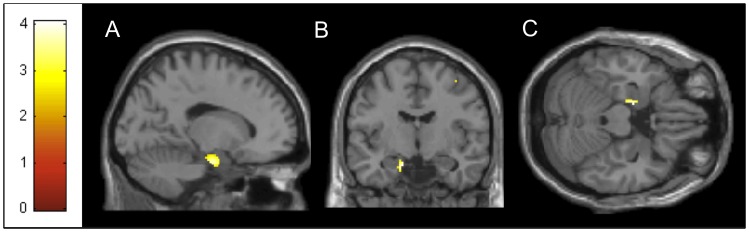

[4] Cha YH, Chakrapani S, Craig A, Baloh RW. Metabolic and functional connectivity changes in mal de debarquement syndrome. PLoS One. 2012;7(11):e49560. doi:10.1371/journal.pone.0049560